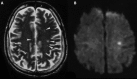

Nipah virus, a paramyxovirus related to Hendra virus, first emerged in Malaysia in 1998. Clinical presentation ranges from asymptomatic infection to fatal encephalitis. Malaysia has had no more cases since 1999, but outbreaks continue to occur in Bangladesh and India. In the Malaysia-Singapore outbreak, transmission occurred primarily through contact with pigs, whereas in Bangladesh and India, it is associated with ingestion of contaminated date palm sap and human-to-human transmission. Bats are the main reservoir for this virus, which can cause disease in humans and animals. There are currently no effective therapeutics, and supportive care and prevention are the mainstays of management.